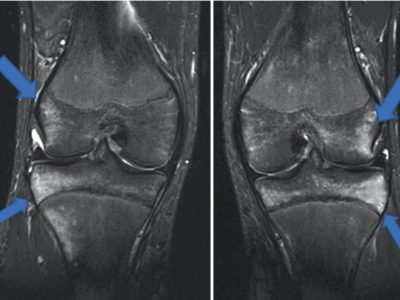

Hautfalte am Knie nach Sportunfall: Was war kaputt?

Ein 48-jähriger männlicher Patient stellt sich nach einem Sportunfall mit Kniegelenksbeteiligung vor. Er war beim Rollschuhhockey mit einem Gegner zusammengestoßen. Er beschreibt starke Schmerzen und ein deutliches Instabilitätsgefühl. Die Haut ist im Bereich des innenseitigen Kniegelenks deutlich eingezogen. Welche Bänder sind gerissen und wie ist es dazu gekommen?

Pincer-Konstellation, Hüftdysplasie und CAM-Impingement im Röntgenbild/© Fehske K / all rights reserved Springer Medizin Verlag GmbH, Sonographiequerschnitt über der Hälfte des M. quadriceps (Normalbefund)/© Gehlen M et al. / all rights reserved Springer Medizin Verlag GmbH, Mediale Meniskusallografttransplantation /© Winkler PW et al. doi.org/10.1007/s43205-025-00320-y unter CC-BY 4.0, Sehnentransplantate zur Rekonstruktion des vorderen Kreuzbands /© Fink C et al. doi.org/10.1007/s00113-025-01551-4 unter CC-BY 4.0, Knie-MRT zeigt überlastungsbedingte Knochenmarködeme/© Brockmeyer M et al. / all rights reserved Springer Medizin Verlag GmbH, Läufer umfasst sein Sprunggelenk/© PeopleImages / Getty Images / iStock (Symbolbild mit Fotomodell), Gruppe beim Rückentraining im Fitnesscenter/© Robert Kneschke / stock.adobe.com (Symbolbild mit Fotomodellen), Walking mit Kniebandage/© Suzi Media Production / Getty Images / iStock (Symbolbild mit Fotomodell), Vordere Kreuzbandruptur/© Springer-Verlag Berlin Heidelberg 2016, Operation zum Kniegelenkersatz/© Issara / stock.adobe.com, Ein kleines Kind hüpft auf einem Trampolin/© anzebizjan / stock.adobe.com (Symbolbild mit Fotomodellen), Anteriore Schulterluxation im Röntgenbild/© Spagna G et al. / all rights reserved Springer Medizin Verlag GmbH, Laufschuh binden/© ssoil322 / stock.adobe.com, Hämatom an der Stirn des 9-Jährigen/© Dr. med. Thomas Hoppen, Innenseitige Hauteinziehung bei eingeschlagenem Innenband/© Akalin ER et al. / all rights reserved Springer Medizin Verlag GmbH, Rekonstruktion der Halswirbelsäule im CT/© Prof. Klaus Schunk, Sonografie am Fußgelenk/© A. Schuh, Gebrochener Fuß im Gips/© Aleksandr Kirillov / stock.adobe.com (Symbolbild mit Fotomodell), Search Icon, Arthropedia, Frau unkenntlich fasst sich ans Knie/© Pornpak Khunatorn / Getty Images / iStock (Symbolbild mit Fotomodell), Ärzteteam führt Hüftoperation durch/© ATRPhoto / stock.adobe.com (Symbolbild mit Fotomodell)